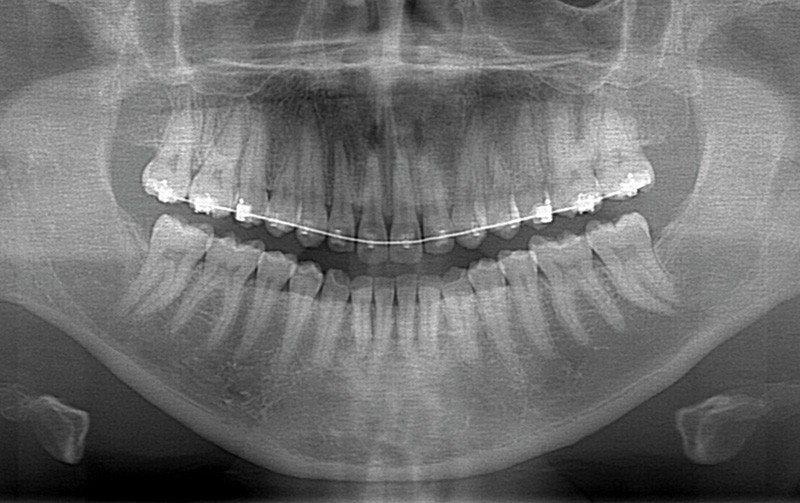

Une patiente de trente ans, traitée orthodontiquement pour une bi-proalvéolie (fig. 1) aggravée par la présence de diastèmes antérieurs et par une supraclusion incisive, consulte pour une hyperplasie gingivale supérieure disgracieuse dans le secteur 14-24 (fig. 2) alors qu’elle est en phase finale (J-60) du traitement orthodontique. L’hyperplasie est apparue au cours du traitement orthodontique dont le but consistait à réduire la projection incisive, à diminuer le sourire gingival par impaction incisivo-canine supérieure et à fermer les diastèmes.

La patiente, outre une allergie au pollen, ne présente pas d’antécédents. L’examen parodontal initial révèle une enveloppe parodontale saine avec une gencive en « peau d’orange » et une pigmentation ethnique ; l’examen radio-clinique du secteur 14-24 met en évidence une hauteur de plus de 3 mm de gencive attachée, des poches vestibulaires et interproximales de 3 à 5 mm sans atteinte osseuse (fig. 3) ni migration de l’attache épithélio-conjonctive.